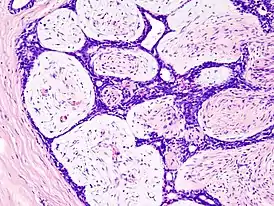

![]() Гистологический препарат фиброаденомы, окраска гемотоксилин-эозином. | |

Гистологические типы

- Интраканаликулярная

- Периканаликулярная

- Листовидная (филлоидная)

Чаще всего встречается смешанный тип строения (интра-, периканаликулярный). Листовидная фиброаденома встречается значительно реже.